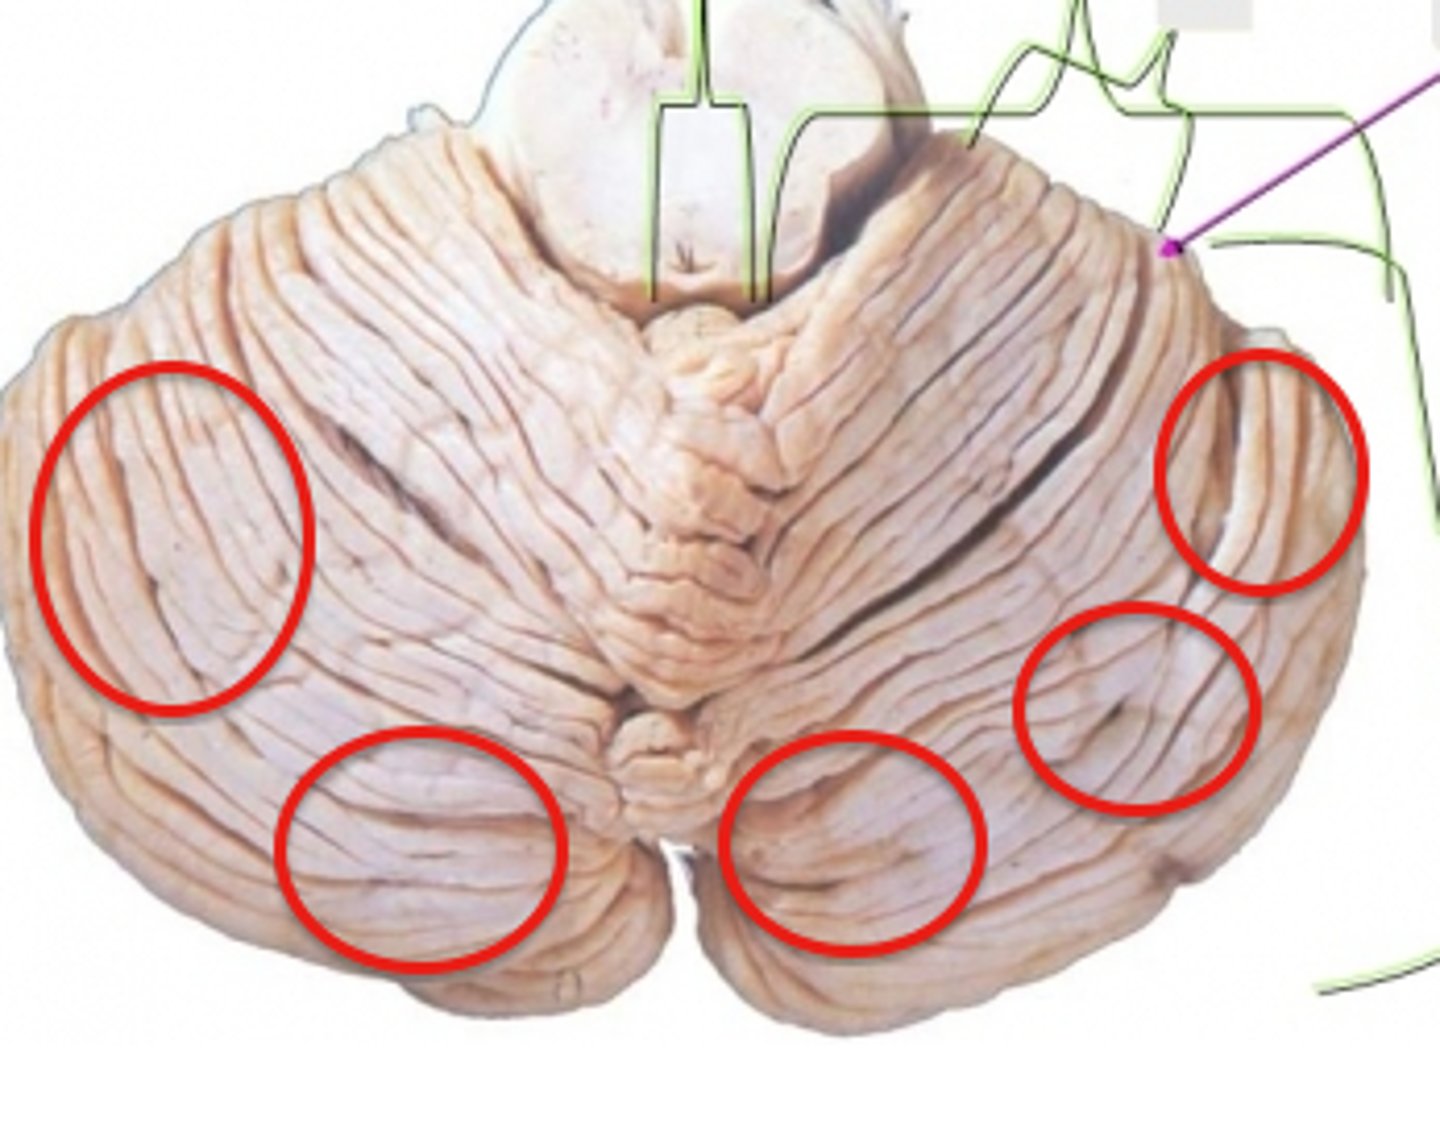

Cerebellum

anterior lobe of cerebellum

posterior lobe of cerebellum

vermis

cerebellar peduncles

folia

arbor vitae

Primary fissure